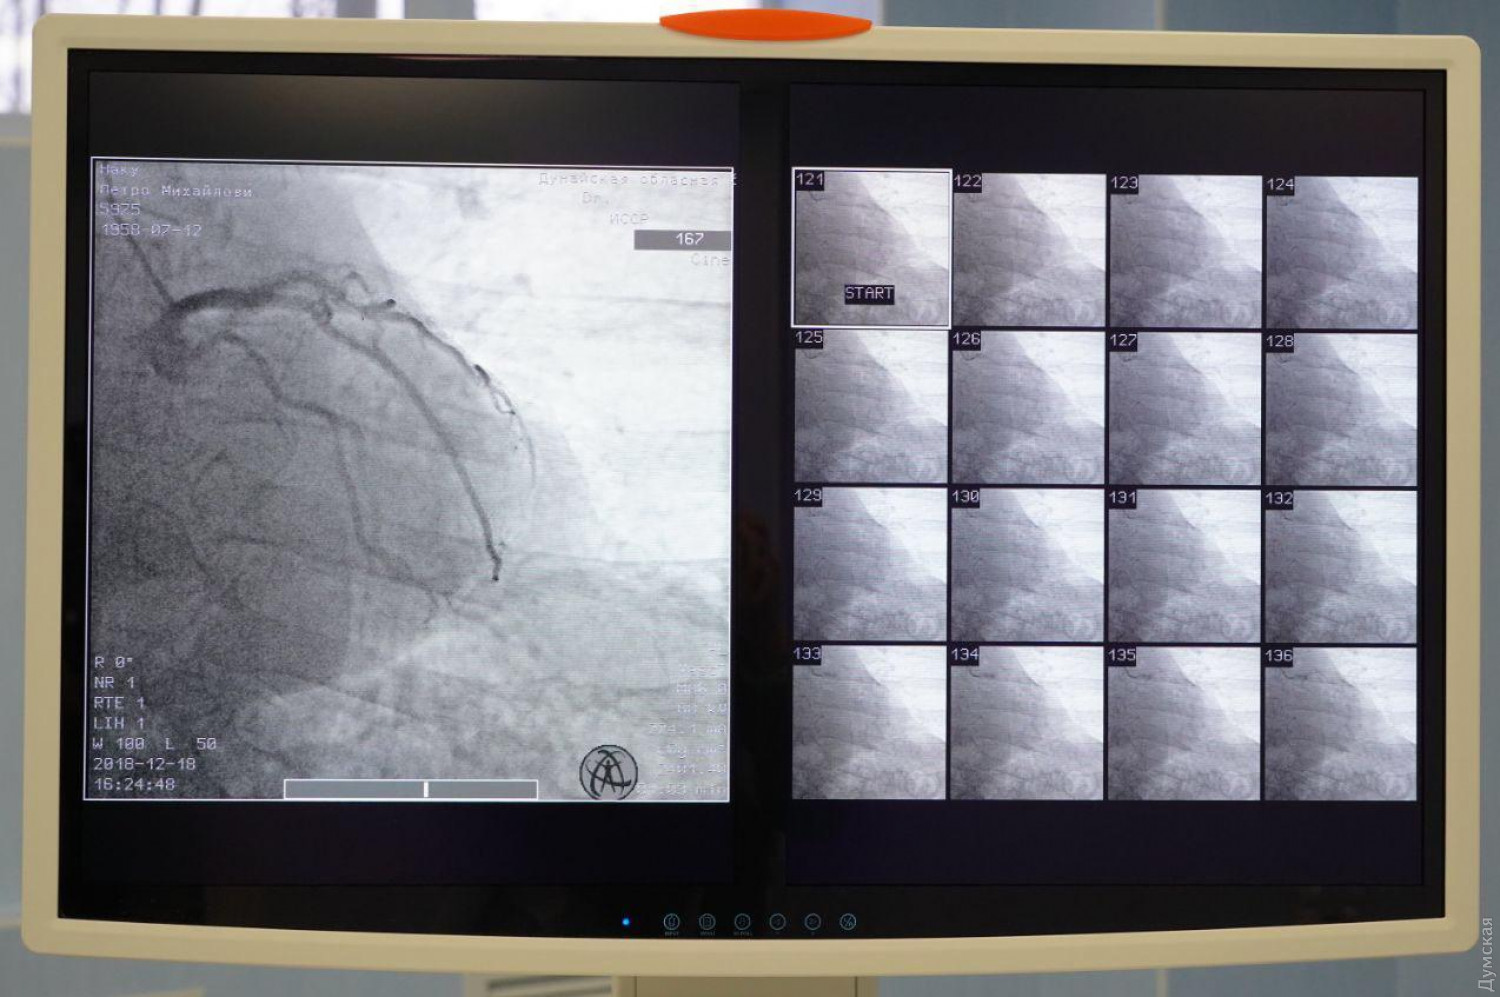

В Измаиле на базе Дунайской областной больницы с сегодняшнего дня заработал современный реперфузионный центр, где жители южных районов смогут круглосуточно получать качественное и своевременное лечение сердечно-сосудистых заболеваний.

Ожидается, что в первый год работы в медучреждении будет проведено 300 диагностических коронарографий и более 100 стентирований.

Центр состоит из ангиографической лаборатории, палаты интенсивной терапии и вспомогательных помещений. На его создание и закупку оборудования из областного бюджета было направлено около 14, 6 миллионов гривен. В штате учреждения — 15 человек: сердечные хирурги, анестезиологи и медсестры, которые прошли профессиональную стажировку.